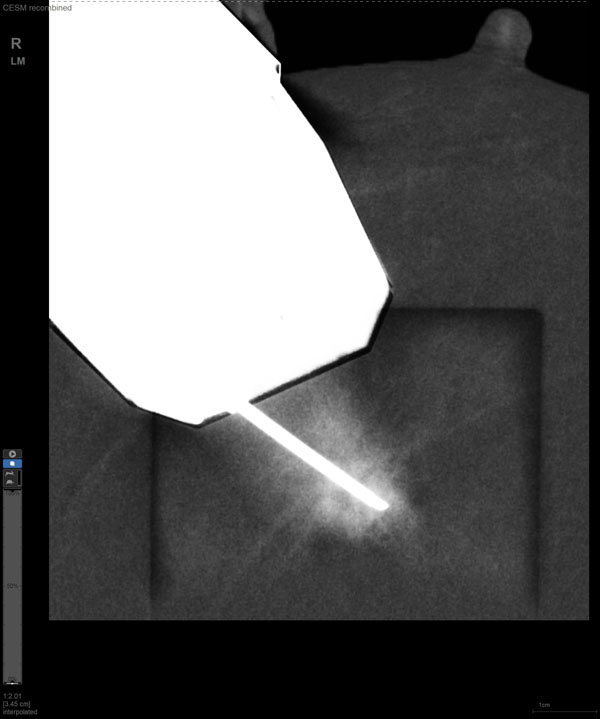

某患者增强磁共振成像MRI显示肿瘤周边有活性,中心区域有组织坏死。为得到准确的病理结果,穿刺靶区需避开肿物坏死区域。在与患者主管医生充分讨论后,放射科医生为患者行CEM引导下穿刺活检术。术中,CEM检查肿物同样显示为环形强化,巧妙避开坏死区域后,穿刺靶区选择了肿物增强早期明显强化区域,术程顺利,仅用时15分钟。术后该患者病理结果为浸润性导管癌Ⅱ级。